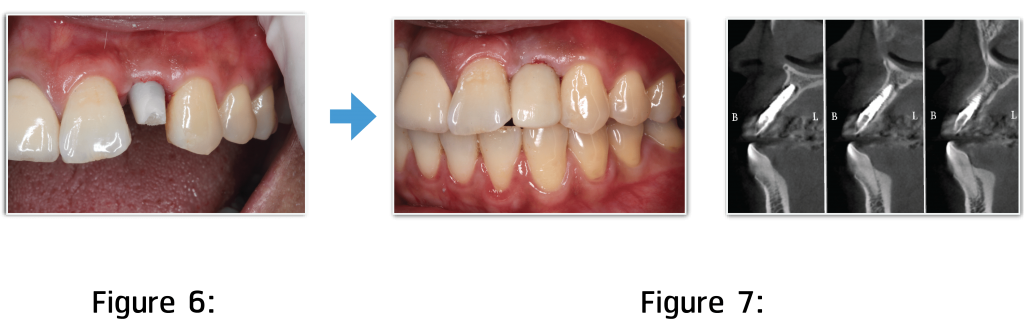

Figure 6:

Permanent crown takes 5 to 7 lab days. In this case, crown was made from monolithic zirconia material which was durable. Before permanent crown is placed, abutment will be placed first as it is used for screw and crown attachment. In this case, abutment was made from zirconia coping material.

Figure 7:

After placing abutment, resin cement will be used to attach with crown. If we see from CT Scan, we will find that implant is in the right position and is related with jawbone position.